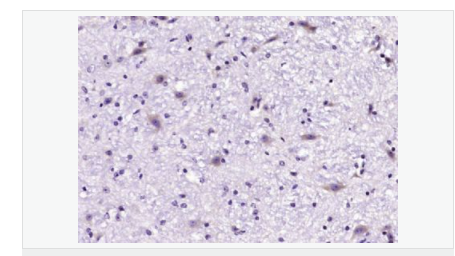

| 產(chǎn)品應(yīng)用 | WB=1:500-2000 IHC-P=1:100-500 IHC-F=1:100-500 ICC=1:100-500 IF=1:100-500 (石蠟切片需做抗原修復(fù)) not yet tested in other applications. optimal dilutions/concentrations should be determined by the end user. |

| 產(chǎn)品介紹 | GLRB (Glycine receptor beta) is a neurotransmitter-gated ion channel concentrated within the spinal cord and brainstem. Expression is also observed in several upper brain regions including the cortex, cerebellum, hippocampus and amygdala. Binding of glycine to GLRB increases the chloride conductance and thus produces hyperpolarization (inhibition of neuronal firing), controlling spinal reflexes and locomotor behavior. Function: The glycine receptor is a neurotransmitter-gated ion channel. Binding of glycine to its receptor increases the chloride conductance and thus produces hyperpolarization (inhibition of neuronal firing). Subunit: Pentamer composed of alpha and beta subunits. Interacts with GPHN Subcellular Location: Plasma membrane; multi-pass membrane protein. DISEASE: Defects in GLRB are the cause of hyperekplexia type 2 (HKPX2) [MIM:614619]. HKPX2 is a neurologic disorder characterized by muscular rigidity of central nervous system origin, particularly in the neonatal period, and by an exaggerated startle response to unexpected acoustic or tactile2 stimuli. Similarity: Belongs to the ligand-gated ion channel (TC 1.A.9) family. Glycine receptor (TC 1.A.9.3) subfamily. GLRB sub-subfamily. SWISS: P48167 Gene ID: 2743 Database links: Entrez Gene: 2743 Human Entrez Gene: 14658 Mouse Omim: 138492 Human SwissProt: P48167 Human SwissProt: P48168 Mouse Unigene: 32973 Human Unigene: 275639 Mouse Important Note: This product as supplied is intended for research use only, not for use in human, therapeutic or diagnostic applications. |